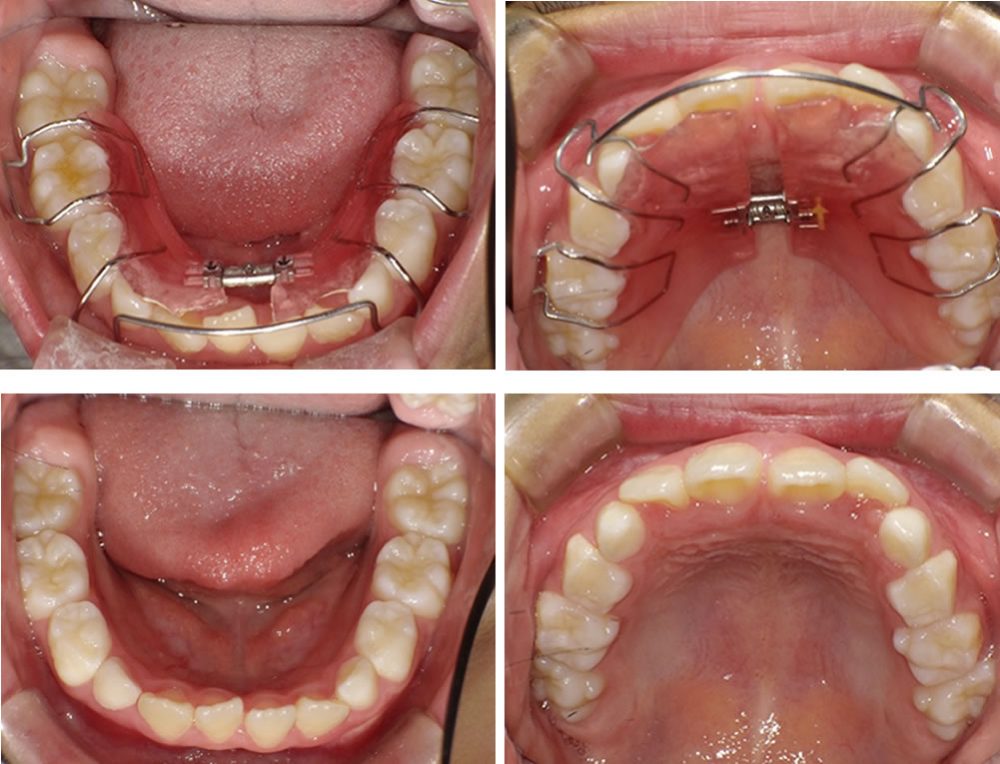

途中経過の写真です。上下どちらも歯が綺麗に並んできました。さらに調節を行っていきます。

さらに期間が経過し、歯並びの状態を確認した写真です。前回の写真と比べると、下顎では乳歯が抜け、4番目の永久歯が生えてきていることが分かります。また、1番目の歯同士もきれいに並び、歯列が整ってきました。上顎では、2番目の永久歯がきれいに歯列に並んできています。

治療完了

最終的な口腔内の状態です。途中経過と比べても、歯並びがさらに改善されたことが分かります。装置は後戻りを防ぐため、リテーナーとして継続して使用していただきますが、乳歯がすべて抜けて永久歯への生え変わりが完了した時点で終了となります。

こちらの患者さまは生え変わりが完了し、矯正治療を終了しました。現在はメンテナンスに通院しながら経過を確認しています。

残っているデコボコした部分を整えるために、必要に応じて再度細かい矯正治療を行うことも可能である旨をお伝えしましたが、現時点では治療結果にご満足いただいております。さらに歯並びを整えたい方は、成人矯正へ移行するケースもあります。